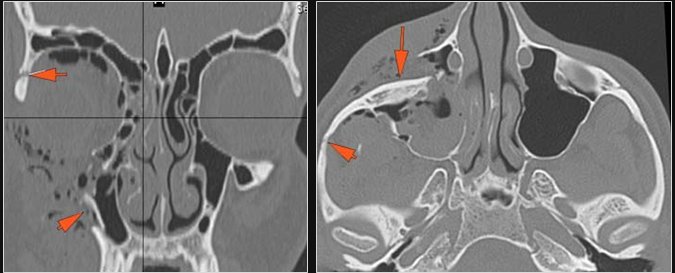

The medial, lateral and posterior maxillary walls are fractured. [Yes/No]

The pterygoid processes of the sphenoid bone are fractured. [Yes/No]

The mesial naso-orbito-ethmoid complex is fractured. Specifically, there is bony injury of the nasal bones or the frontal process of the maxilla and the medial walls of the orbit are abnormal. [Yes/No]

There is injury of the ethmoid complex. Specifically, the ethmoid roof, olfactory fossa and the cribriform plate are fractured and/or significantly dehiscent. [Yes/No]

The frontal bone and frontal sinus inner and outer tables are fractured. [Yes/No]